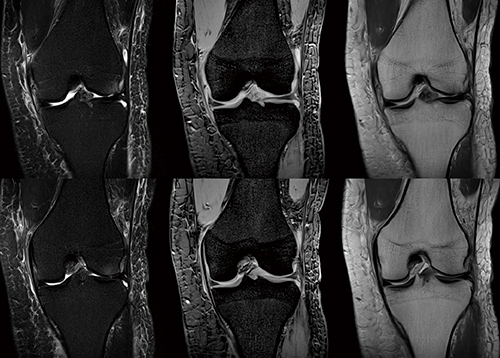

図1 膝の拡大画像

16chフレキシブルSPEEDERは、患部に密着させることができるため、高いSNRを得ることが可能。高SNRを生かした高分解能撮像になり、軟骨構造が明瞭に描出されている。